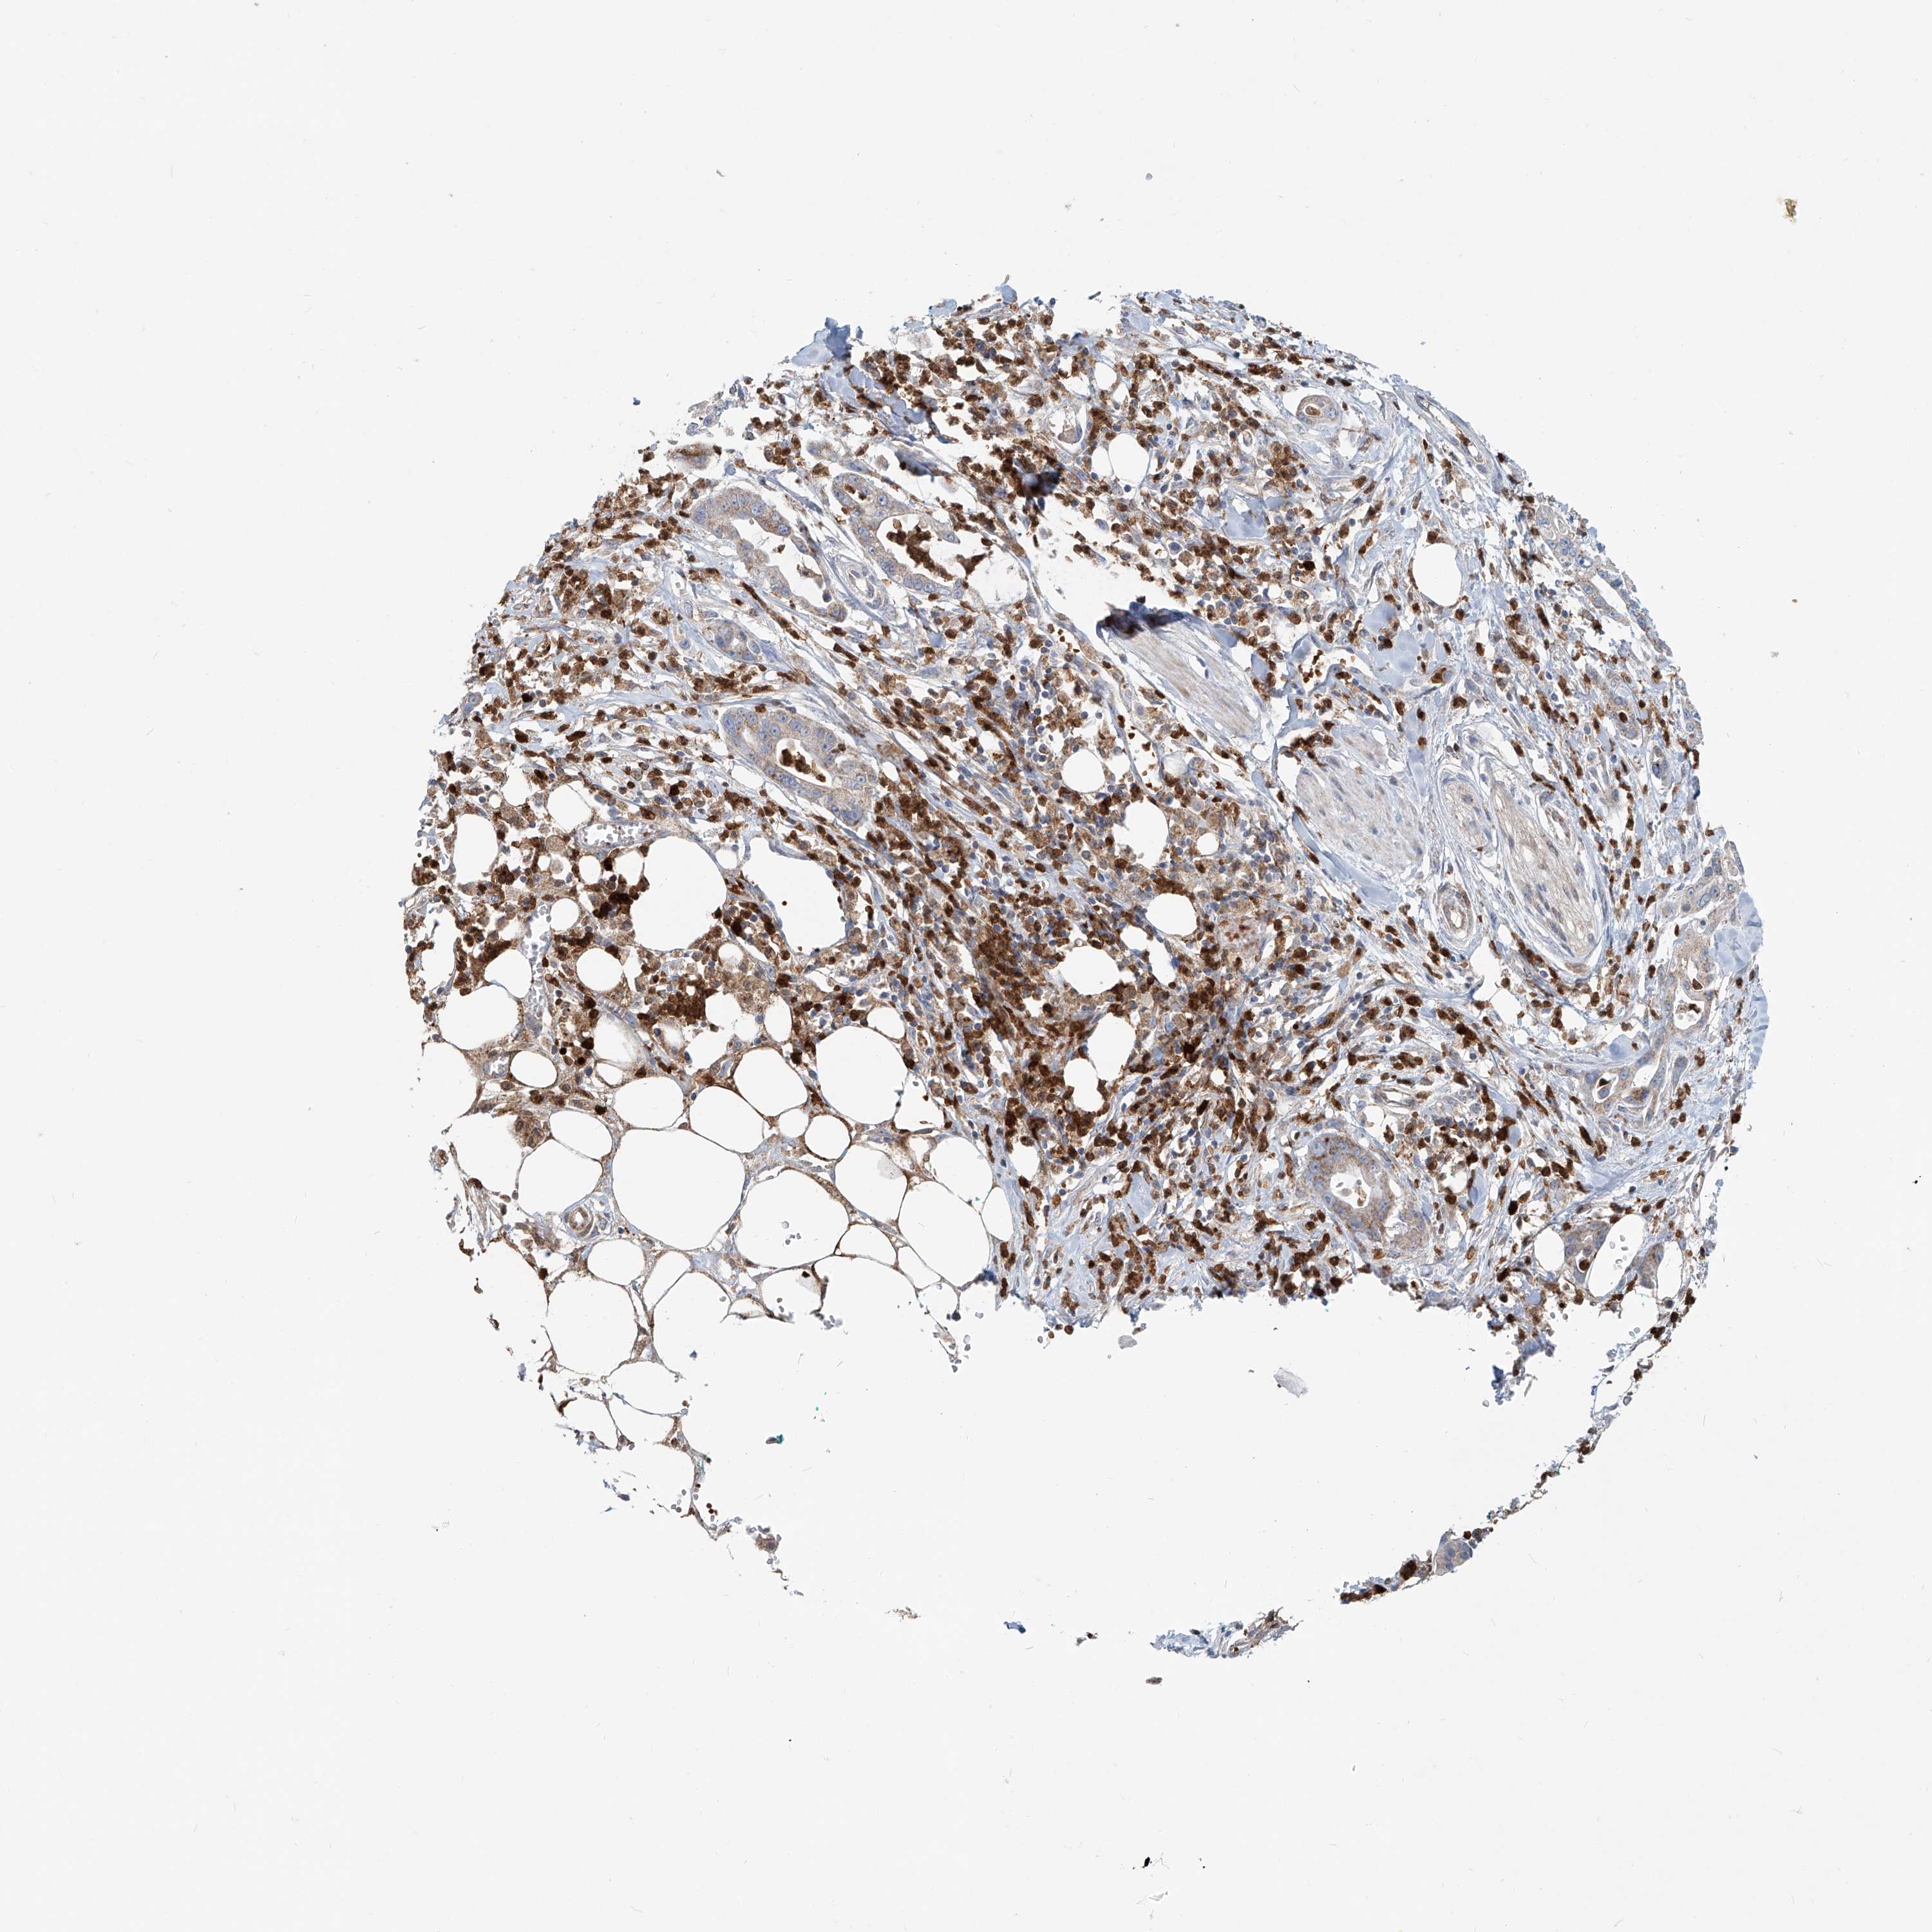

PANCREATIC CANCER - Protein expressioni

A mouse-over function shows sample information and annotation data. Click on an image to view it in a full screen mode. Samples can be filtered based on level of antibody staining by selecting one or several of the following categories: high, medium, low and not detected. The assay and annotation is described here.

Note that samples used for immunohistochemistry by the Human Protein Atlas do not correspond to samples in the TCGA dataset.

Antibody stainingi

Antibody staining in the annotated cell types in the current human tissue is reported as not detected, low, medium, or high, based on conventional immunohistochemistry profiling in selected tissues. This score is based on the combination of the staining intensity and fraction of stained cells.

Each image is clickable and will lead to virtual microscopy that enables deeper exploration of all samples and also displays staining intensity scores, fraction scores and subcellular localization as well as patient and tissue information for each sample.

Antibody HPA029412

Antibody CAB034366

Staining

High

Medium

Low

Not detected

Intensity

Strong

Moderate

Weak

Negative

Quantity

>75%

75%-25%

<25%

None

Location

Nuclear

Cytoplasmic/membranous

Cytoplasmic/membranous,nuclear

Adenocarcinoma, NOS